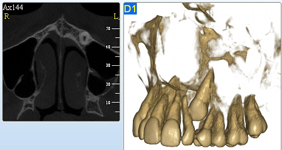

Je speciální zubní digitální tříprostorový tomograf (3D), který umožňuje na základě jediného snímkování vytvořit všechny typy RTG zobrazení, které jsou pro lékaře potřebné. Díky používané technologii tzv. „kuželového paprsku“ a speciálním senzorům je výrazně zmenšená dávka záření - o více jak 80% proti klasickému CT vyšetření. To je významné zejména u dětí. Pomocí tohoto přístroje je možné zjisti skutečnou situaci v čelistních kostech pacienta tedy množství kosti - můžeme změřit skutečnou šířku i výšku kosti, i kvalitu kosti (hustotu) v místě uvažované implantace. 3D (tříprostorové) zobrazení umožňuje zvýšit prostorovou představu operatéra ještě před vlastní operací a zároveň pacientovi lépe objasnit a ukázat oblast plánovaného zavedení implantátu.

Pacient „neumí číst“ RTG snímky, ale díky 3D zobrazení vidí „svoji skutečnou čelist“ - např. jak je nízká či úzká, vidí průběh nervu nebo velikost čelistní dutiny, což mu umožní i pochopení nutnosti v některých případech provést pomocné zákroky ještě před vlastním zavedením implantátu (viz. kostní štěp, sinus lift, kostní granulát...).

Jedná se o nejnovějším přístroj ze skupiny dentálních hybridních CBCT (3D) + 2D (pan i ceph) systémů. Opět umožňuje na základě jediného snímkování vytvořit všechny typy RTG zobrazení, které jsou pro lékaře potřebné. Používaná technologii tzv. „kuželového paprsku“ a speciální senzory pro minimální zátěž při snímkování pacienta.

Vyšetření pomocí tohoto přístroje (nebo 3D DVT - NewTom) a získaná data používáme pro každou implantaci, dále ve stomatochirurgii (zlomeniny čelistí, zuby moudrosti, cysty, onemocnění čelistního kloubu), ortodoncii (retinované zuby, nadpočetné zuby), parodontologii atd.